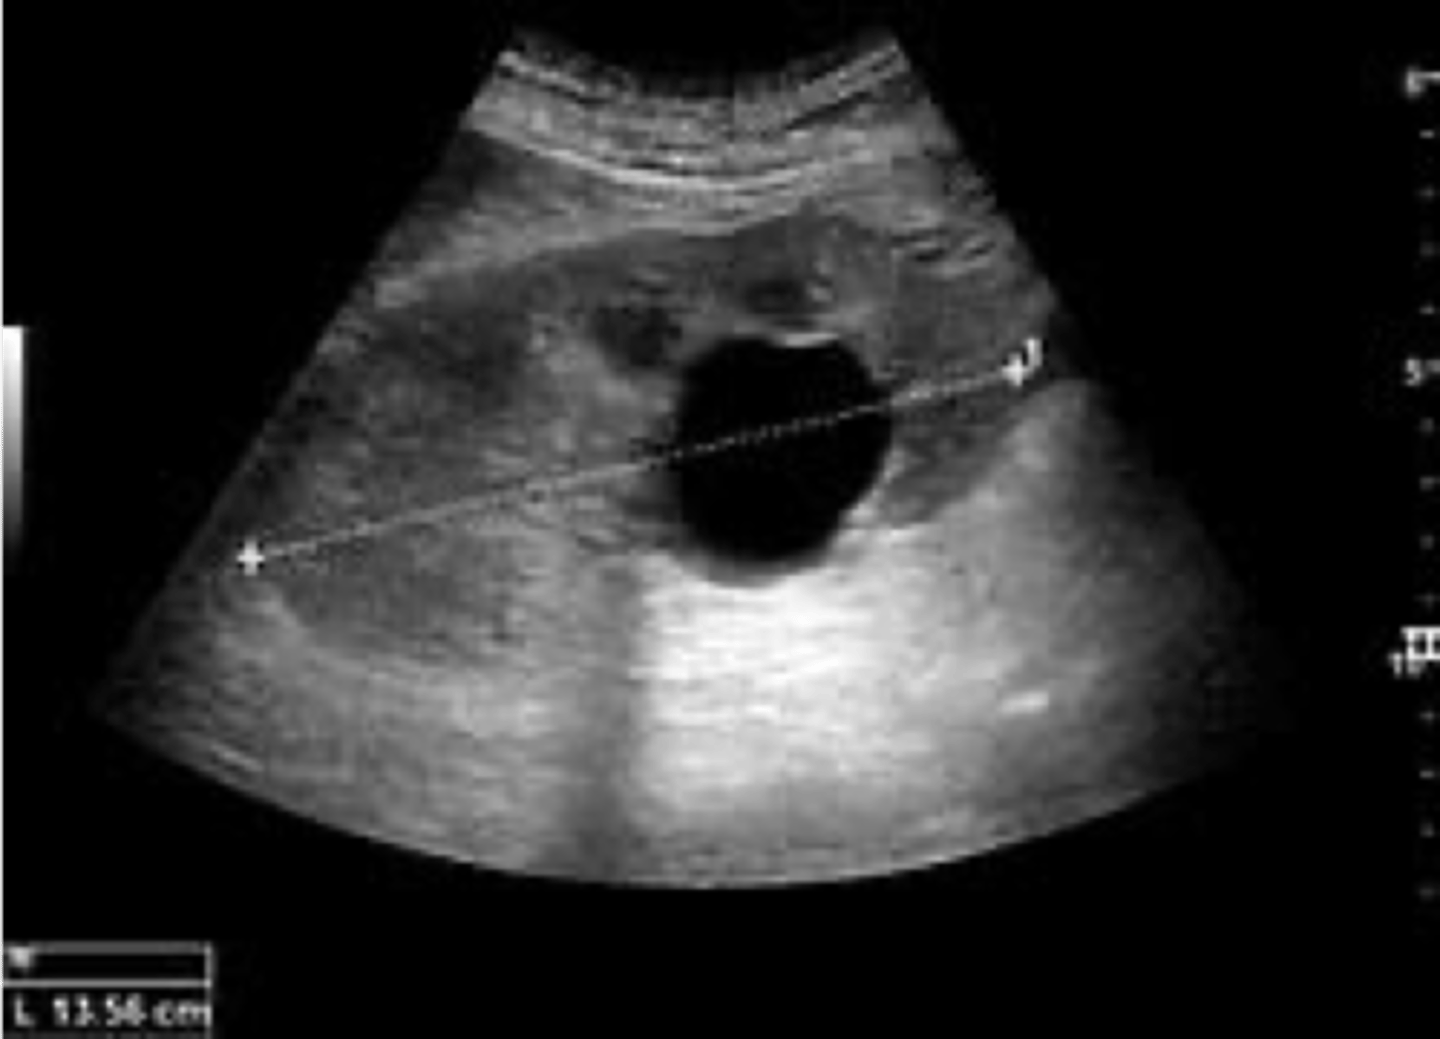

simple renal cyst

What disorder:

-most common renal mass

-solitary, multiple, and BL

-smooth appearing with translucent fluid per CT imaging, anechoic on US

-occurs most often in pts >50 y/o

-often seen on screening US

-range in size from <1 cm - 10 cm

-usually does not compromise renal function

-usually 1 epithelial layer without renal elements

-need to rule out more serious disorders!

-Tx: usually none required

-pain is rare, acetaminophen/NSAIDs short course if renal function is preserved

-rare if ever aspiration and surgery

-infection is rare

ID